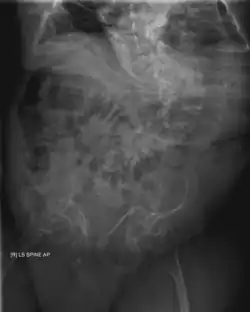

Diagnosis

Diagnosis is typically based on medical imaging, including plain X-rays, and symptoms. In severe OI, signs on medical imaging include abnormalities in all extremities and the spine.[97] As X-rays are often insensitive to the comparatively smaller bone density loss associated with type I OI, DEXA scans may be needed.[5]: 1514

An OI diagnosis can be confirmed through DNA or collagen protein analysis, but in many cases, the occurrence of bone fractures with little trauma and the presence of other clinical features such as blue sclerae are sufficient for a diagnosis. A skin biopsy can be performed to determine the structure and quantity of type I collagen. While DNA testing can confirm the diagnosis, it cannot absolutely exclude it because not all mutations causing OI are yet known and/or tested for.[83]: 491–492 OI type II is often diagnosed by ultrasound during pregnancy, where already multiple fractures and other characteristic features may be visible. Relative to control, OI cortical bone shows increased porosity, canal diameter, and connectivity in micro-computed tomography.[98] OI can also be detected before birth by using an in vitro genetic testing technique such as amniocentresis.[99]